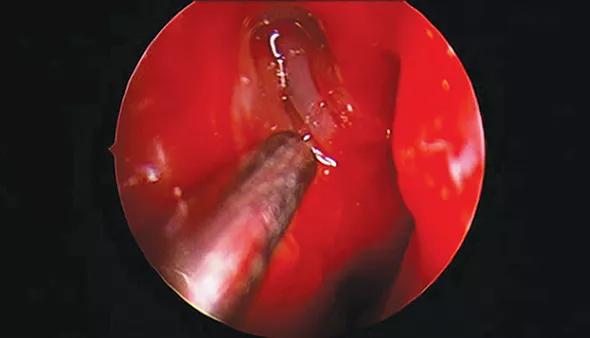

An incision is made in the lateral nasal wall mucosa, anterior to the insertion of the middle turbinate. The mucosa is elevated, and part of the frontal process of the maxilla and lacrimal bone is removed with endoscopic drills and instruments to allow visualization of the sac. The sac is incised and subsequent intubation of the nasolacrimal system is performed (Figure).

Figure. Endoscopic view (via 4-mm rigid endoscope) after osteotomy and lacrimal sac incision (right) in a 22-month-old patient undergoing endoscopic DCR. The middle turbinate is on the right.